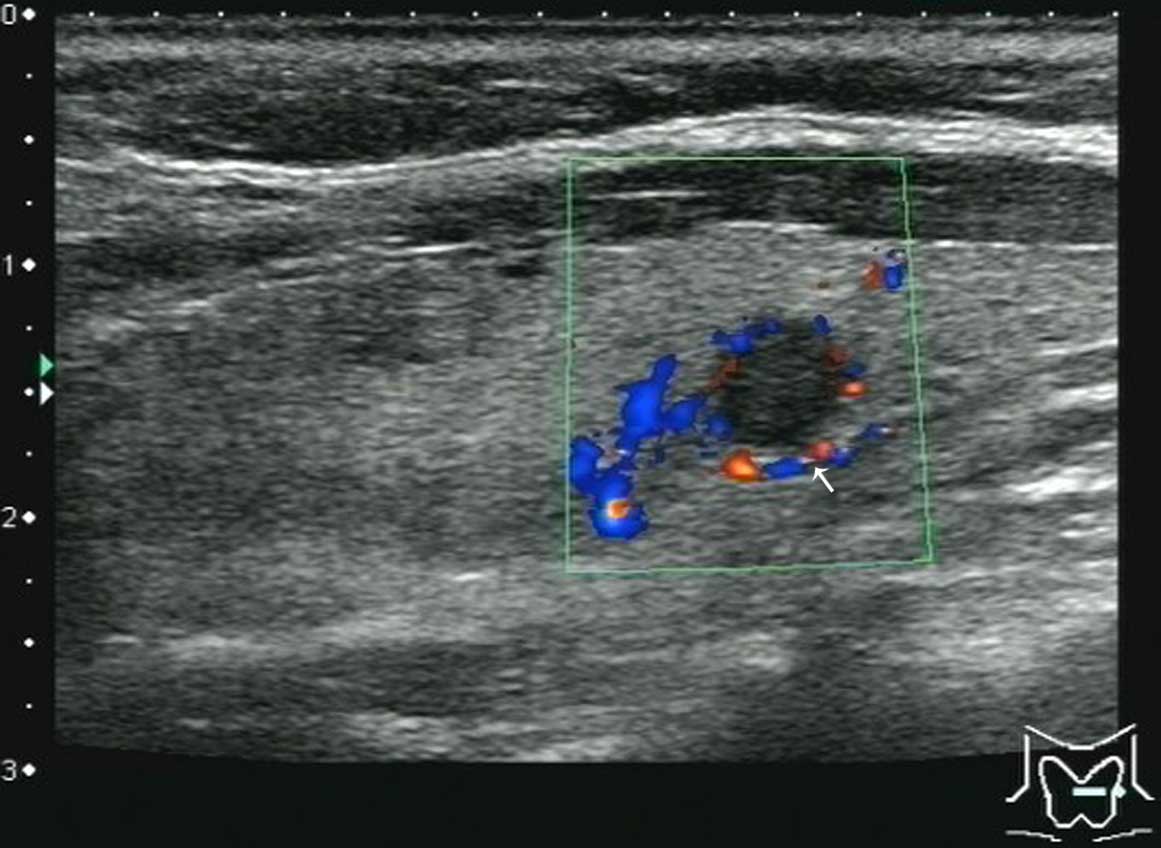

Colour Doppler image of. The image of both the thyroid nodule and the surrounding thyroid tissue can present as red color affecting a large part of the thyroid gland beyond the nodule under. 23 and npv 100 vs.

Papillary Thyroid Carcinoma A Color Doppler Ultrasound Showing Download Scientific Diagram

Role Of Color Doppler Us A Transverse Gray Scale Image Of Download Scientific Diagram